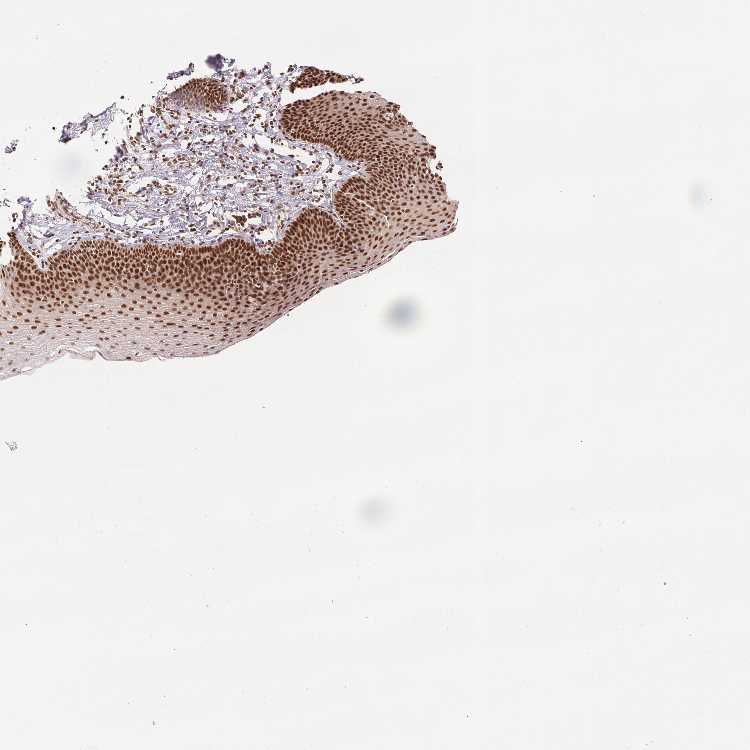

Antibody HPA048798

Squamous epithelial cells High